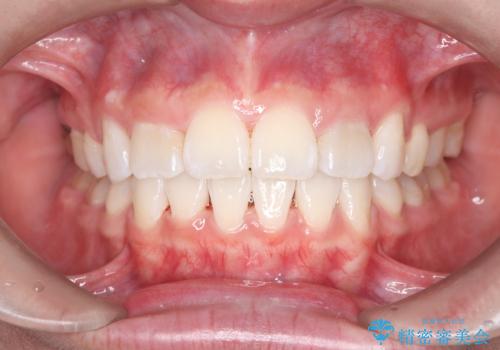

突き出た前歯を下げて理想的な横顔に。上下左右4番抜歯による審美ワイヤー矯正

担当医 河口智英